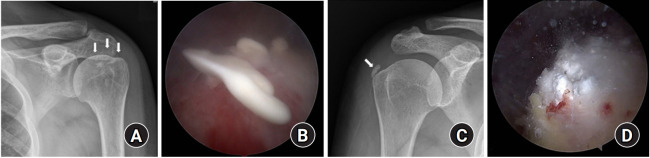

Fig. 2.

Arthroscopic decompression and rotator cuff repair using side-to-side sutures. (A) Preoperative fat suppressed T2-weighted magnetic resonance imaging coronal view shows calcific deposits on the supraspinatus tendon within musculotendinous junction. (B) Arthroscopic findings after removal and debridement of calcific deposits lesion and an approximately 1.0×1.0-cm-sized defect is seen. (C) Arthroscopic side-to-side suture is performed using polydioxanone .

측면-측면 봉합을 이용한 관절경적 감압술 및 회전근개 봉합술. (A) 수술 전 지방 억제 T2 가중 자기공명영상 관상면에서 상근건과 건근 접합부 내 석회화 침착물이 관찰됨. (B) 석회화 병변 제거 및 절제술 후 관절경 소견으로 약 1.0×1.0cm 크기의 결손이 확인됨. (C) 폴리디옥사논을 이용한 관절경적 측면-측면 봉합술 시행.